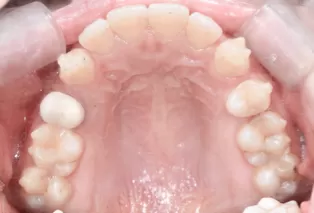

Photos intra-orales